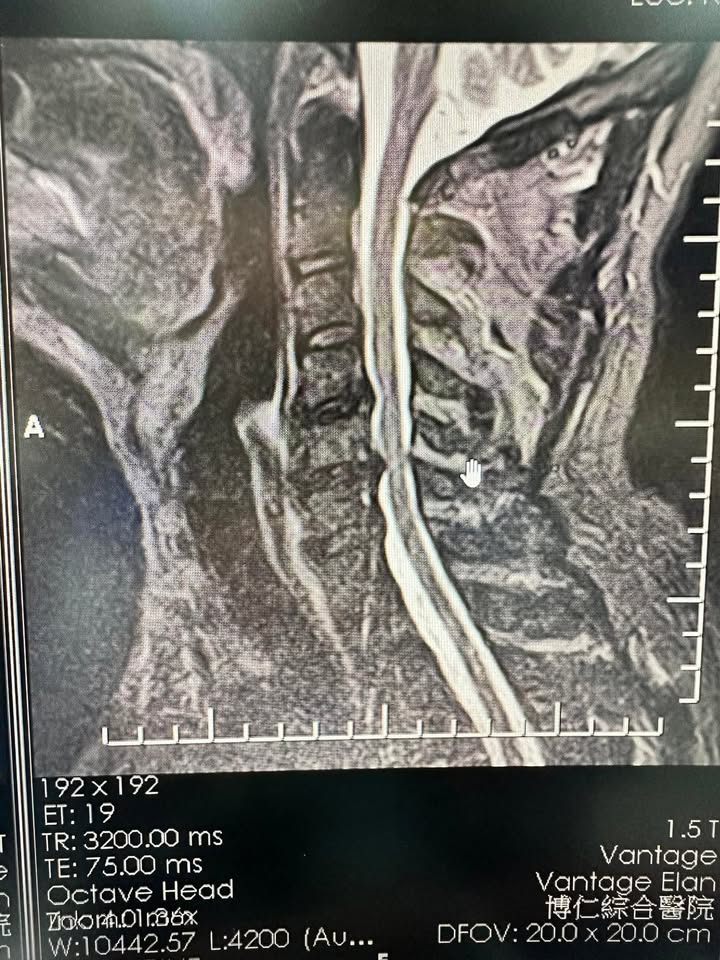

初次見面,張先生的臉上寫滿了疲憊和不安。他告訴我們,他不僅肩頸僵硬得像一塊石頭,還有頭暈、耳鳴和胃脹氣,甚至連睡覺時都會感到胸悶。我們立即為他安排了核磁共振檢查,結果顯示,他的頸椎從第二節到第七節,幾乎全線病變,壓迫著交感神經,成為這些症狀的罪魁禍首。

▶️ 「交感神經型頸椎病」是一種由頸椎退化、變形或壓迫交感神經引起的綜合症狀。頸椎內的交感神經控制多種重要功能,當受到壓迫或刺激時,可能導致頭暈、耳鳴、胸悶、心悸、視力模糊、胃脹氣等不適症狀。這種病症通常與長期的不良姿勢、頸椎受傷或退化有關。診斷通常需藉助核磁共振等影像學檢查,確定病變位置與嚴重程度。治療以非手術為主,包括頸椎減壓、針刀療法及最後考慮神外手術調整,幫助釋放神經壓迫並改善症狀。針對早期病變,及時治療可以顯著提升生活質量,減少進一步惡化的風險。